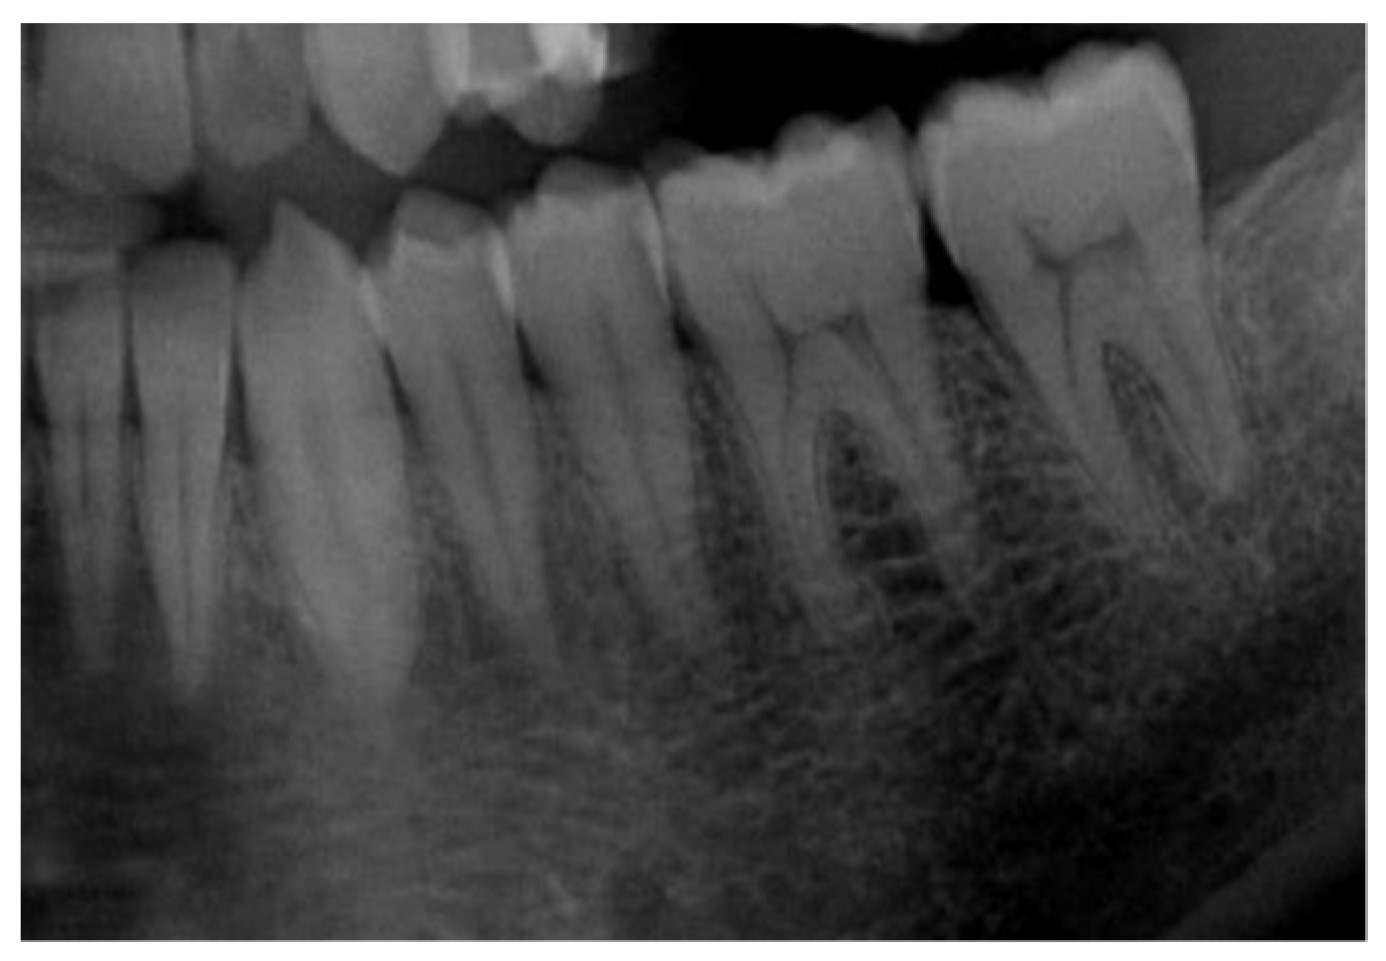

| Input image | Panoramic Radiograph | 2D Panoramic Radiograph images |

| Stages of teeth development | Categorical | Stages of the seven left lower mandibular teeth |